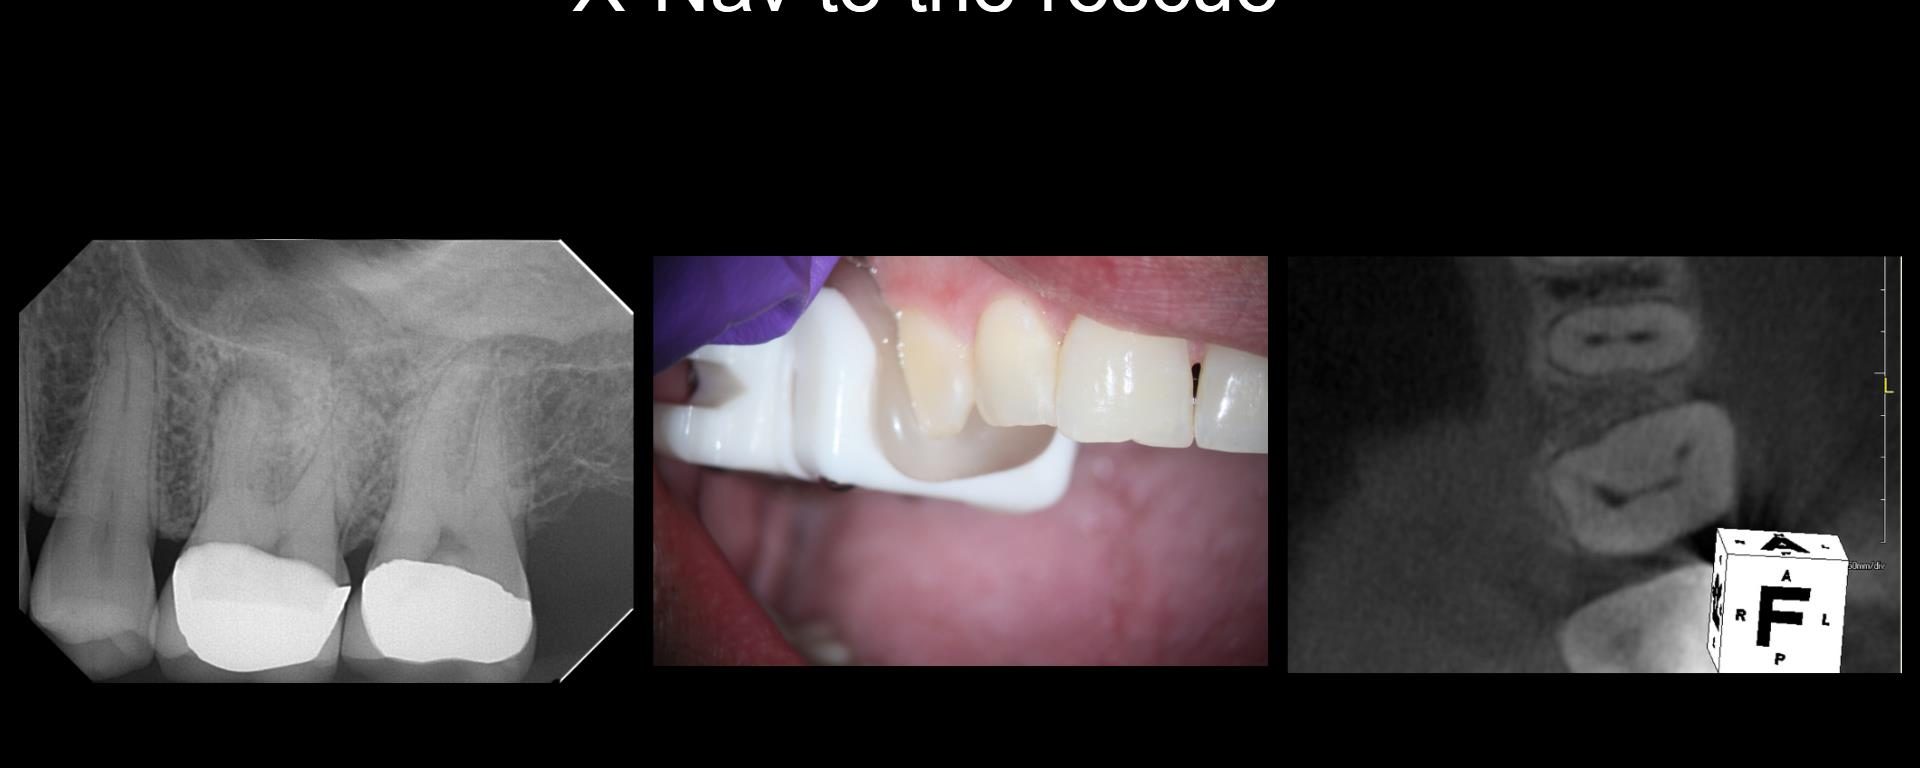

X-Nav today

Because this was a Zirconia crown, my approach was to make a “staging platform” where I thought the access points would be. Proabbaly made the platform larger than I needed to. In this case, the X-nav was spot-on. I’m nowhere near Charles or Pushpak, but I am getting more comfortable with it. This took longer […]